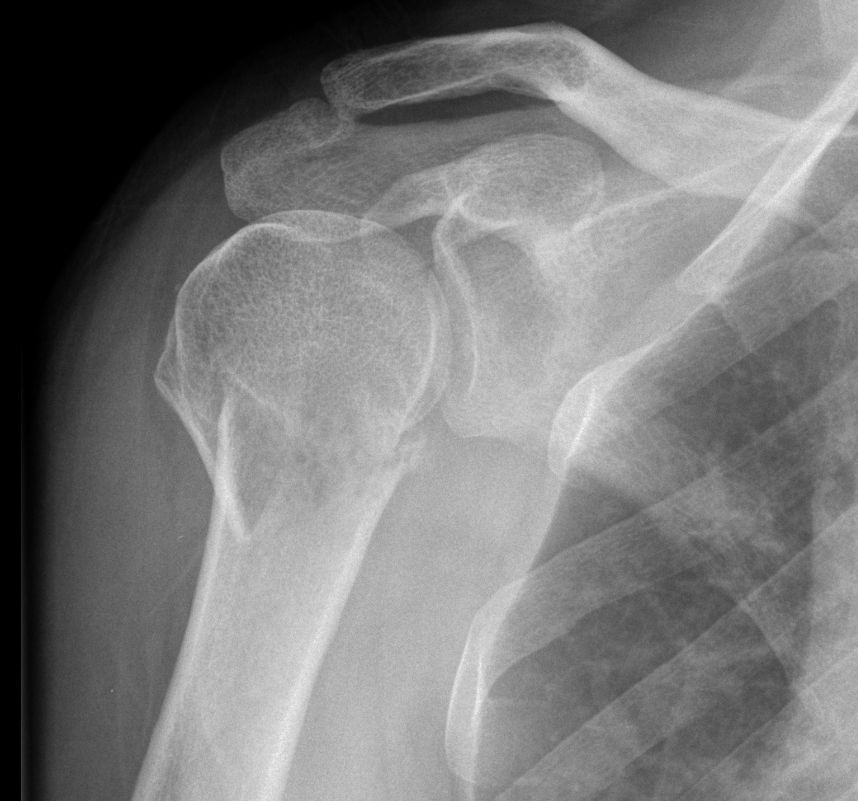

70-jährige Frau mit ossär metastasiertem

Mammakarzinom. Wolkige Verkalkungen im Humeruskopf. Osteoblastische Metastasen.![]() |